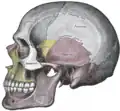

Kraniet set fra siden | |

Kraniet set forfra |

Kraniet kan opdeles i to dele: hjernekassen (også kaldt neurokraniet), der indeholder hjernen og beskytter denne, og ansigtsskelettet, der er medvirkende til at danne ansigtet, og dermed indeholder både næsehulen og øjenhulen.

Hjernekassen dannes af nedenstående seks knogler:

- Isseben (1 par, Latin: Os parietale)

- Kileben (Os sphenoidale)

- Nakkeben (Os occipitale)

- Pandeben (Os frontale)

- Siben (Os ethmoidale)

- Tindingeben (1 par, Os temporale)

Hjernekassen beskrives som regel ved at opdele denne i to dele kaldet theca cranii og basis cranii, hvor sidstnævnte beskrives som hhv. basis cranii interna og basis cranii externa. Theca cranii er den del af kraniet, der kan ses oppefra, basis cranii externa er den del af kraniet, der kan ses nedefra, når underkæben er fjernet, og basis cranii interna er den del af kraniet, der kan ses oppefra, når theca cranii er fjernet.

Der findes følgende knogler i ansigtsskelettet:

- Overkæbeben (1 par, maxilla)

- Underkæbeben (mandibula)

- Tungeben (Os hyoideum) – (halsknogle.)

- Ganeben (1 par, Os palatinum)

- Næseben (1 par, Os nasale)

- Tåreben (1 par, Os lacrimale)

- Plovskærben (Vomer)

- Kindben (1 par, Os zygomaticum)

- Det nedre muslingeben (1 par, Concha nasalis inferior)

Ansigtsskelettet er den del af kraniet, der kan ses forfra, og består derfor udover ovennævnte knogler også af pandebenet (den del, der kaldes squama frontalis)